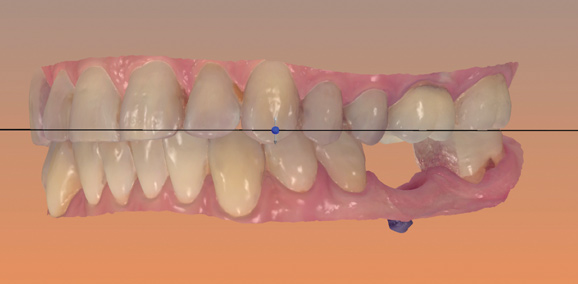

Fig 5. Screen capture of an intraoral scan obtained with a wireless intraoral scanner.

Figure 5